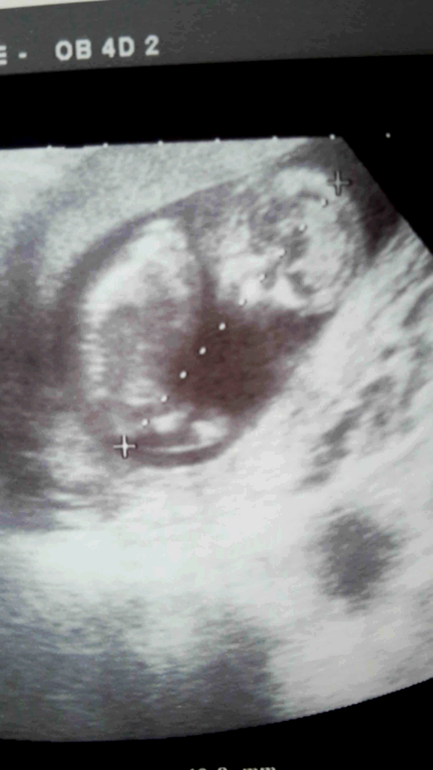

УЗИ вначале начали вагинально и ни шиша)))))говорит высоко убежал уже малш не видно толком😂потом отвели уже на кушетку через животик смотреть...аааа не могу как мило это видить❤❤❤фасолинка уже вовсе не фасолинка человечек прям такой даже боксёр какой то😂😂непоседа

Пока головку замеряли спинку позвоночник итд замер непоседа и тишина ...потом Г смеётся и говорит вот уселся как казачонок😂😂😂говорю есть причина ... дед же казах😂😂Вообщем по паспорту сегодня 13+5 по УЗИ примерно 12 недель ...всё правельно от зачатия если брать день Овуляции то знаю)))))....вообщем вотЬ наш Деть какой большой/ая знакомьтесь

тут спинкой сидит к датчику)))) стесняшка....

Кстати, очень отчетливо все на снимке видно, и глазки и ротик, и гол.мозг. Красота!!!

на плазме шикарно всё смотрелось на бумаге уже не так конечно но я и этому безумно рада)))каждый день снимочки расматриваю)))